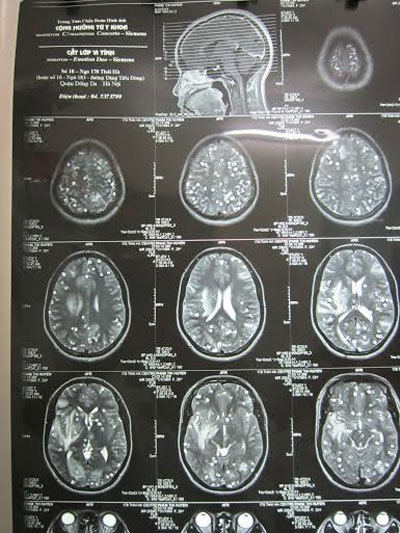

Khoái món nem thính, bệnh nhân P.T.H. cũng phải nhập viện với triệu chứng co giật, đau đầu, buồn nôn. Sau khi cho chụp phim, các bác sĩ phát hiện rất nhiều nang sán ở trên não người bệnh. Được biết, bệnh nhân ở vùng Bắc Ninh, có thói quen ăn nem thính làm từ thịt nạc sống.

Những nốt tròn trong có nhân là nang sán lợn làm tổ dày đặc trong não bệnh nhân (Ảnh: Zing.vn) |

Tương tự, ông Nguyễn Hồng C. (59 tuổi) ở Tiên Lãng, Hải Phòng cũng bị đau đầu, buồn nôn, người gầy sút cân. Sau khi đi khám, bác sĩ phát hiện ông bị nhiễm ấu trùng sán lợn. Ấu trùng đã làm tổ trong não đè vào dây thần kinh thăng bằng khiến ông hay chóng mặt, đau đầu.